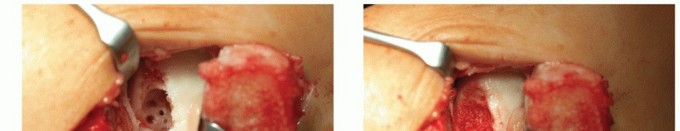

Using a curette, harvest two or three full-thickness articular grafts that include the superficial layer of subchondral bone (TECH FIG 1). The grafts are transferred to a sterile container and transported to the laboratory. Using a patented procedure, the articular cartilage matrix is enzymatically disrupted to isolate the chondrocytes. Culturing of chondrocytes requires about 2 to 6 weeks, depending on the company and the preferred culturing process.

- TECH FIG 1 • A. Harvesting cartilage with a curette from the ventral aspect of the talus. B. Grasping the small piece of cartilage for culturing.